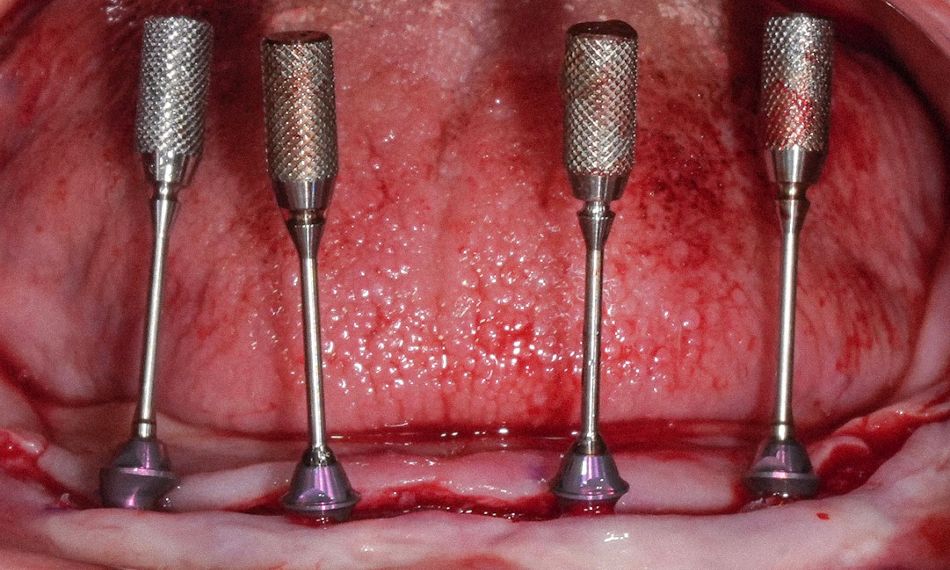

In this region, two tilted and two axial implants were placed freehand. Straumann® Roxolid® SLActive® implants were inserted according to the surgical plan to achieve optimal primary stability. The following implants were placed: #32 – Straumann® BLX Ø3.75 mm, length 10 mm; #35 – Straumann® BLX Ø3.75 mm, length 12 mm; #42 – Straumann® BLX Ø3.75 mm, length 10 mm; and #45 – Straumann® BLX Ø3.75 mm, length 12 mm (Fig. 12).

Implants were placed with a torque of 35 Ncm, which suggests that adequate primary stability was achieved (Fig. 13). The postoperative view showed correct alignment and integration after implant placement, with proper soft tissue adaptation and satisfactory implant positioning in relation to the planned prosthetic restoration (Fig. 14).